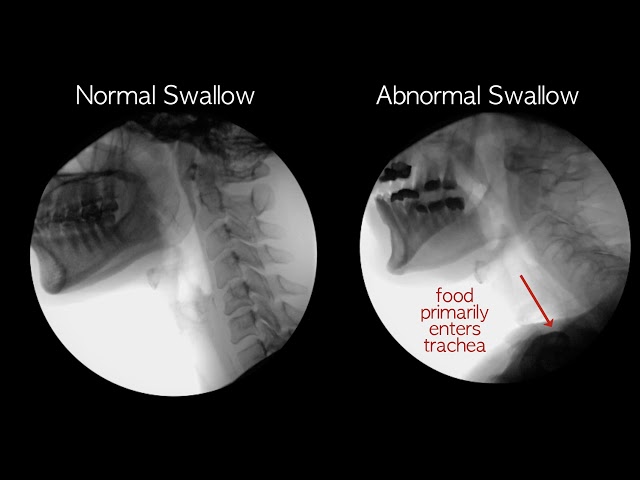

آزمایش مطالعه بلع

در این آزمایش، بیمار مایع حاوی باریم را میبلعد و سپس سری از اشعه ایکس برای ارزیابی فرآیند بلع گرفته میشود.